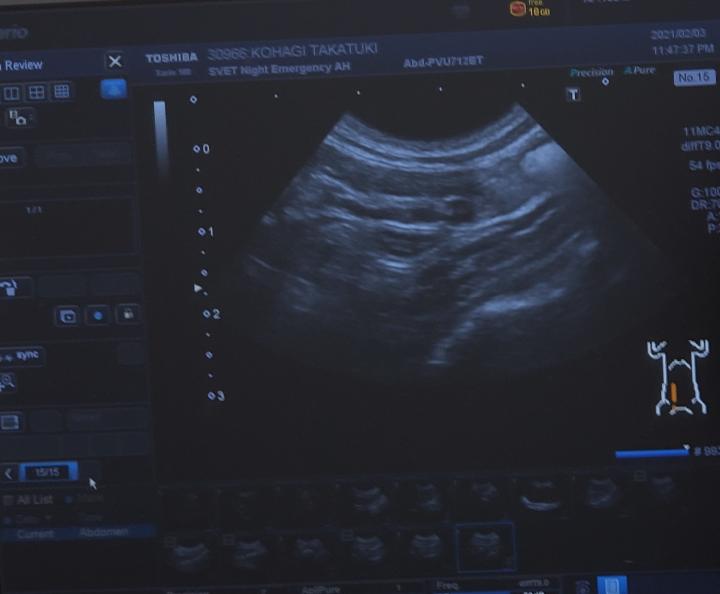

点滴は必須。エコーと血液検査のうち、エコーだけはやってもらうことにしました。待つこと20分。

胃腸炎で、胃腸の動きが弱ってるけど腸閉塞では無いそうです。でも、このまま食べない、元気がないが続くと危ないから、明日は様子見てお医者さんに連れていくように言われました。